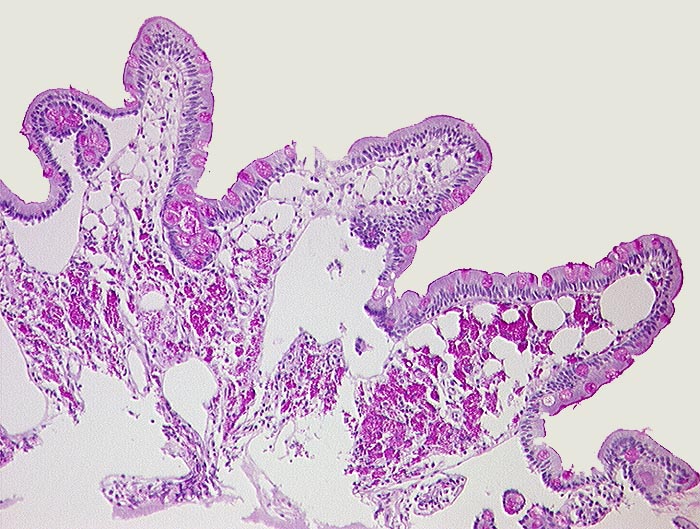

AP/ Morbus Whipple

Morbus Whipple

Dünndarm